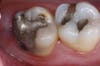

Mercury (as in a thermometer) expands and contracts with change in temperature, every time you consume anything hot or cold. This amalgam filling is sitting in a tooth that resembles glass or china. This chunk of metal then expands and contracts within this brittle tooth. So what do you think it will do to the tooth surrounding this material? That’s right, it will cause fractures. Fractures can break the tooth. How many of you have had a crown because your tooth broke but the filling was still intact?! Fractures also will leak, allowing bacteria to penetrate within, causing decay (cavities). The photos I have posted to this blog clearly show what we see when we remove the amalgam.